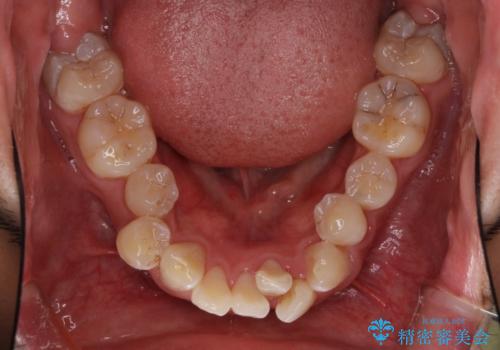

前歯の叢生を解消 ワイヤー装置での抜歯矯正

- 前歯の叢生と八重歯を気にして来院された患者様です。

叢生が強く、奥歯の咬合も左右差が大きかったため、上下左右4本を抜歯して、ワイヤー矯正を行うこととしました。